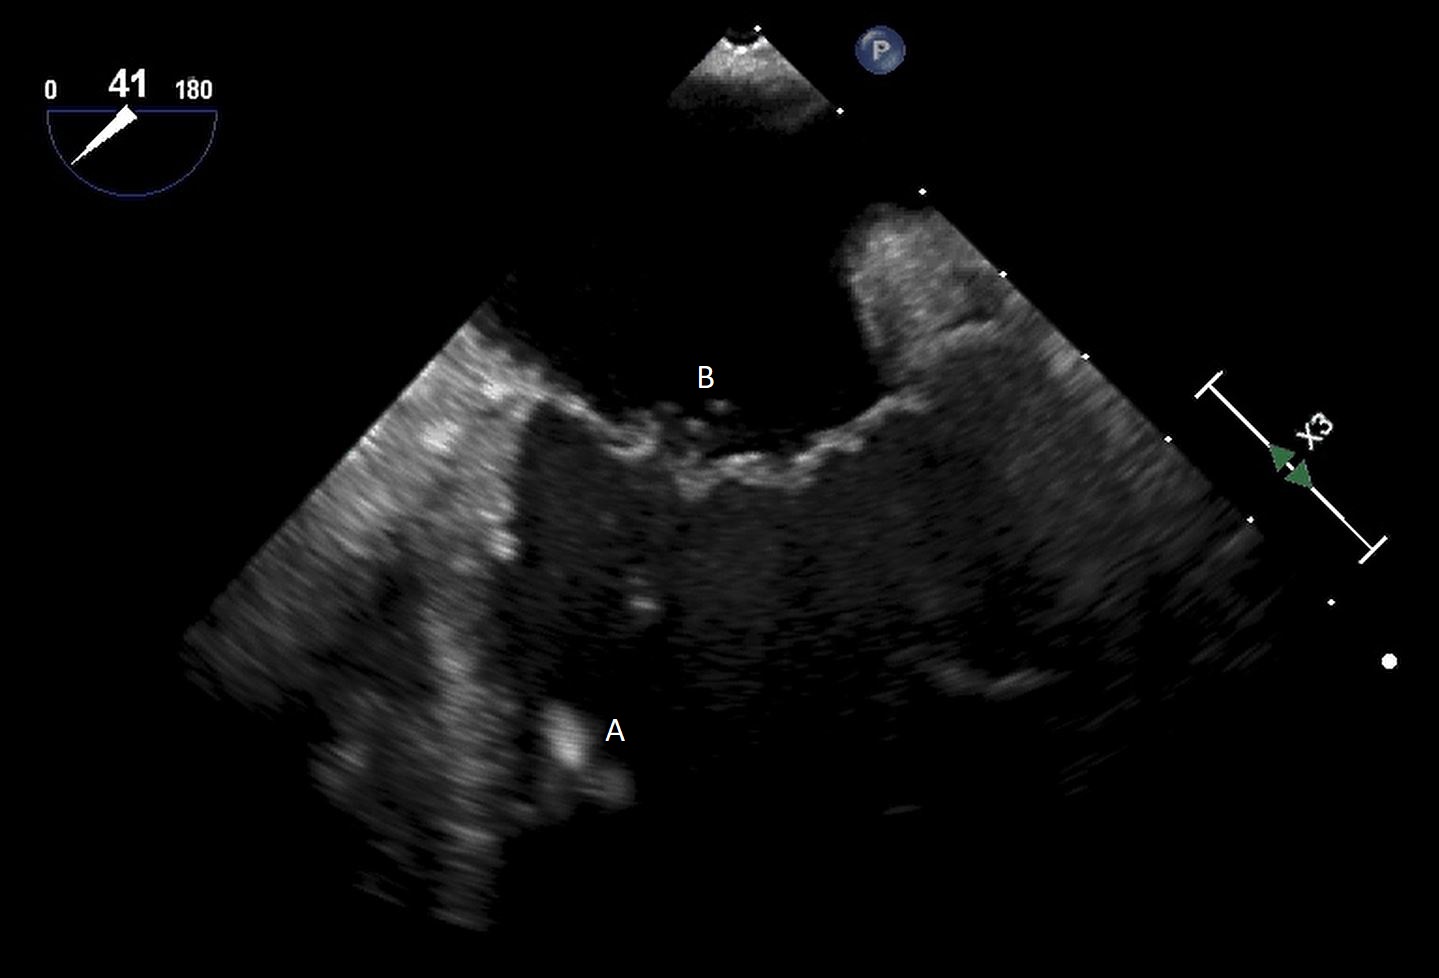

The TandemHeart Protek Duo is a percutaneous right ventricular assist device (RVAD) placed via a dual-lumen 29 French sheath in the right internal jugular vein. The inflow lumen is situated in the right atrium and outflow lumen in the main pulmonary artery. The port lumens are connected externally to a TandemHeart centrifugal pump [31]. As this is generally placed in the operating room, intra-operative TEE can be used to help guide placement. Similar to the Impella RP, bicaval and midesophageal 4 chamber views can visualize the inflow cannula and RV inflow-outflow view and upper esophageal views can be used to visualize the outflow cannula (Figs. 13,14,15). On occasion, its placement can result in distortion of the tricuspid valve morphology with resultant tricuspid regurgitation (Fig. 16). If this is noted, cannula repositioning can be considered. TEE can also help in identifying the ideal pump speed for a patient on TPD support. When utilizing a “ramp protocol”, where the pump speed is progressively increased intraoperatively, midline interventricular septal position can indicate an appropriate amount of RV support [32].

Fig. 15.Real time 3D TEE imaging of the RV inflow outflow view demonstrating the Protek Duo in the RVOT. (A) Protek Duo. (B) RVOT. (C) Aortic valve.